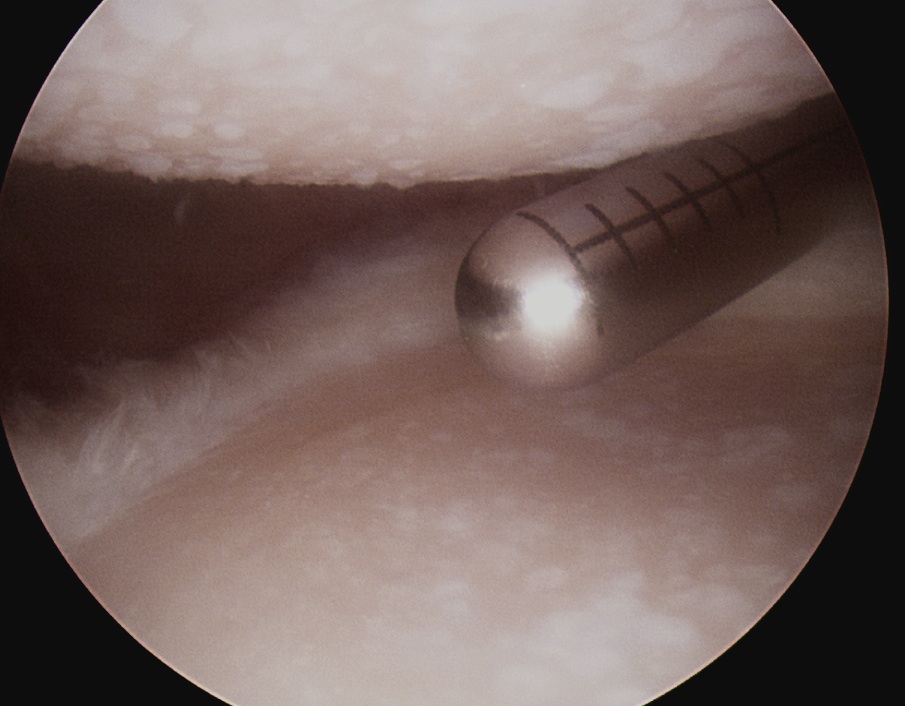

Subacromial space

Portals

| Posterior | Lateral subacromial portal |

|---|---|

|

Redirect posterior portal Under acromion |

Midportal clavicle |

| Usually viewing portal |

Rotator cuff repair / Subacromial decompression Distal clavicle resection |

![]() |